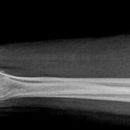

Unterarm seitlich

Patient sitzt seitlich am Tisch, Oberarm und Unterarm ulnar aufliegend im Winkel von 90°, Hand streng seitlich , Daumen liegt auf den Metacarpalen.

Senkrecht auf Unterarm- und Filmmitte.

Radius und Ulnar müssen sich weitgehend decken. Dies ist aber nur möglich, wenn man den Unterarm so einstellt wie HG seitlich.

Anmerkung zur Qualitätskriterien umändern. Und dazu: dargestellte Nachbargelenke sollen rein seitlich abgebildet sein.